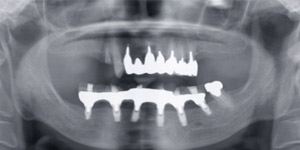

![]() |

治療前のレントゲンです。 |